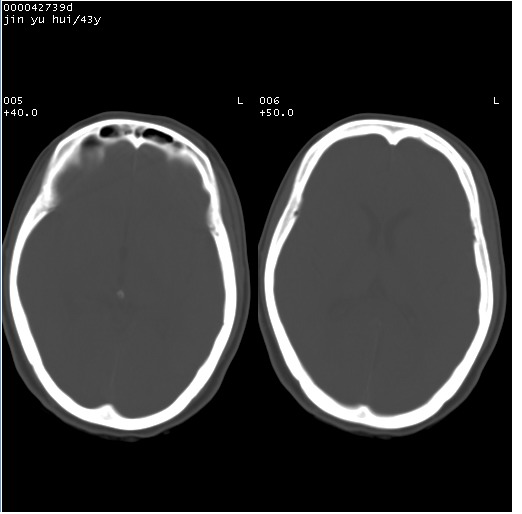

患者 女,43岁。头部外伤26天,经住院治疗,现头痛减轻。申请ct复查,了解颅内情况。

临床诊断:2级脑外伤。

颅脑ct轴位平扫(层厚、层距均为10mm),图像如下:

伴硬膜下水瘤

硬膜下水瘤

纵裂旁硬膜下水瘤,左额部头皮肿胀

大脑镰左旁硬膜下血肿慢性期。

大脑镰左旁慢性硬膜下血肿.